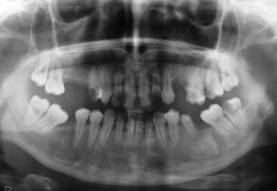

Cazul 2: L.A., fem:

Initial clinic si radiologic se observa prezenta resturilor radiculare frontale superioare.

Radiografii retroalveolare la inceputul si la sfīrsitul tratamentului endodontic